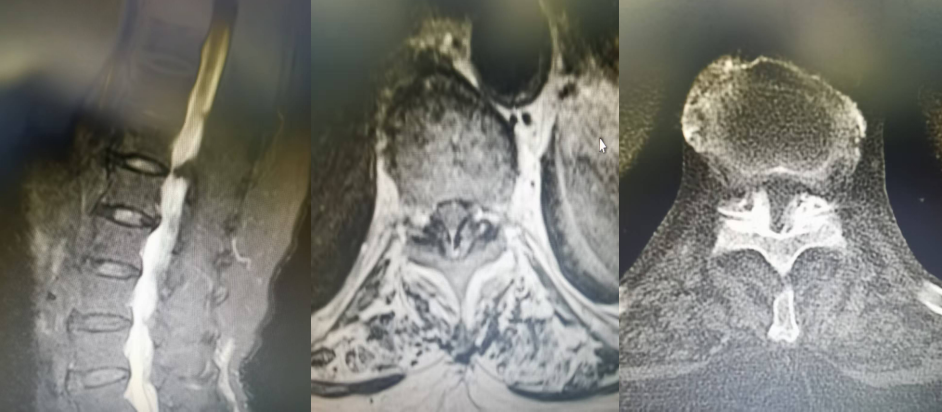

患者,女,82歲,T10/11黃韌帶鈣化并椎管狹窄,且伴有嚴(yán)重的骨質(zhì)疏松,術(shù)前雙下肢麻木、無力,不能正常行走。如果實施開放性手術(shù)需行全身麻醉下全椎板切除減壓內(nèi)固定治療,由于患者年齡大、耐受差,手術(shù)失敗率極高,經(jīng)過科室討論后決定給予微創(chuàng)手術(shù)治療。手術(shù)由郝清海副主任醫(yī)師主刀,在劉濤副主任醫(yī)師配合下順利完成UBE內(nèi)鏡下的黃韌帶鈣化物去除,椎管擴(kuò)大,脊髓減壓治療。手術(shù)切口約1.5cm,且能保留患者的運動單元,術(shù)后患者無明顯腰背痛癥狀,神經(jīng)功能有極大恢復(fù),可自主下地行走,療效確切,患者及家人對手術(shù)效果非常滿意。

T10/11黃韌帶鈣化,椎管狹窄,硬膜囊受壓嚴(yán)重,腦脊液不通暢

患者術(shù)后復(fù)查CT及MRI均顯示脊髓無明顯受壓,腦脊液通暢,術(shù)后患者下肢肌力級感覺明顯恢復(fù),已能下地行走